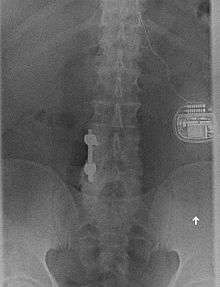

![]() Anterior view X-ray of a spinal cord stimulator (SCS) implanted in the thoracic spine |

A spinal cord stimulator is a device used to exert pulsed electrical signals to the spinal cord to control chronic pain. Further applications are in motor disorders. The lumbar spinal cord is a preferred target for the control of spinal spasticity[1][2] or augmentation of standing and stepping capabilities.[3][4][5][6] Spinal cord stimulation (SCS), in the simplest form, consists of stimulating electrodes, implanted in the epidural space, an electrical pulse generator, implanted in the lower abdominal area or gluteal region, conducting wires connecting the electrodes to the generator, and the generator remote control. SCS has notable analgesic properties and, at the present, is used mostly in the treatment of failed back surgery syndrome, complex regional pain syndrome and refractory pain due to ischemia.